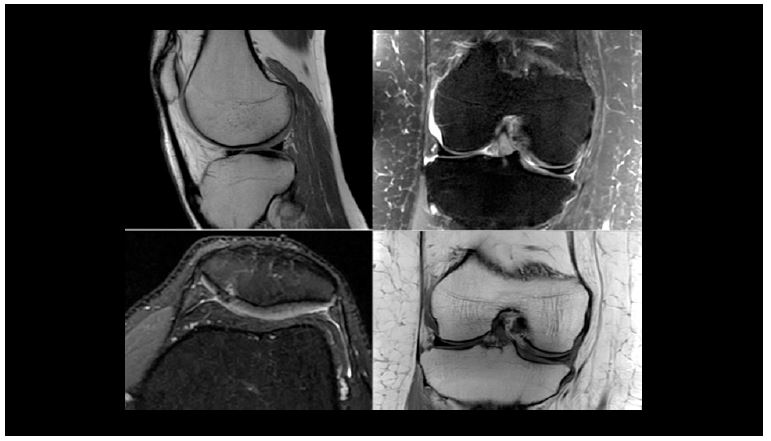

Клінічні зображення МСК з використанням 16-канальної гнучкої котушки

Рис. 11. Зображення коліна.